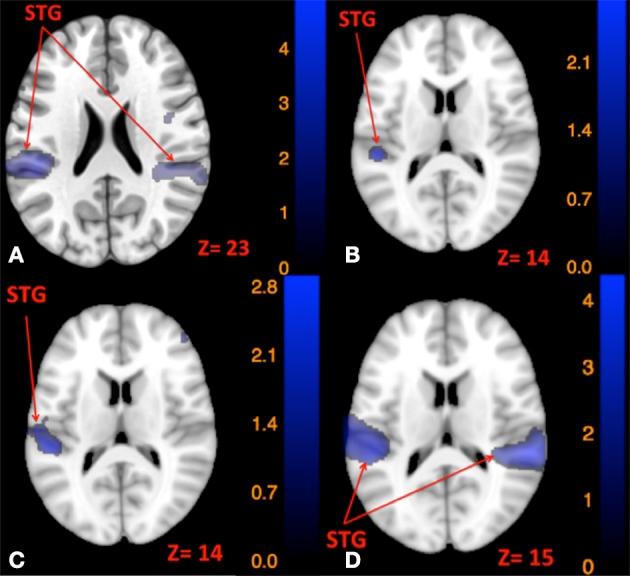

The current study characterizes brain fMRI activation in response to two modes of vestibular stimulation: Skull tap and auditory tone burst. The auditory tone burst has been used in previous studies to elicit either a vestibulo-spinal reflex [saccular-mediated colic Vestibular Evoked Myogenic Potentials (cVEMP)], or an ocular muscle response [utricle-mediated ocular VEMP (oVEMP)]. Research suggests that the skull tap elicits both saccular and utricle-mediated VEMPs, while being faster and less irritating for subjects than the high decibel tones required to elicit VEMPs. However, it is not clear whether the skull tap and auditory tone burst elicit the same pattern of brain activity. Previous imaging studies have documented activity in the anterior and posterior insula, superior temporal gyrus, inferior parietal lobule, inferior frontal gyrus, and the anterior cingulate cortex in response to different modes of vestibular stimulation. Here we hypothesized that pneumatically powered skull taps would elicit a similar pattern of brain activity as shown in previous studies. Our results provide the first evidence of using pneumatically powered skull taps to elicit vestibular activity inside the MRI scanner. A conjunction analysis revealed that skull taps elicit overlapping activation with auditory tone bursts in the canonical vestibular cortical regions. Further, our postural control assessments revealed that greater amplitude of brain activation in response to vestibular stimulation was associated with better balance control for both techniques. Additionally, we found that skull taps elicit more robust vestibular activity compared to auditory tone bursts, with less reported aversive effects, highlighting the utility of this approach for future clinical and basic science research.

当前的研究描述了大脑功能磁共振成像(fMRI)对两种前庭刺激模式的激活反应:轻敲颅骨和听觉短音。在先前的研究中,听觉短音已被用于引发前庭脊髓反射[球囊介导的绞痛性前庭诱发肌源性电位(cVEMP)]或眼肌反应[椭圆囊介导的眼前庭诱发肌源性电位(oVEMP)]。研究表明,轻敲颅骨可引发球囊和椭圆囊介导的VEMPs,同时与引发VEMPs所需的高分贝音调相比,对受试者来说速度更快且刺激性更小。然而,尚不清楚轻敲颅骨和听觉短音是否会引发相同的大脑活动模式。先前的影像学研究记录了在不同前庭刺激模式下,脑岛前后部、颞上回、顶下小叶、额下回和前扣带回皮质的活动。在此,我们假设气动轻敲颅骨会引发与先前研究中所示类似的大脑活动模式。我们的结果首次证明了在MRI扫描仪内使用气动轻敲颅骨来引发前庭活动。联合分析显示,轻敲颅骨在典型的前庭皮质区域引发与听觉短音重叠的激活。此外,我们的姿势控制评估表明,两种技术中,对前庭刺激反应时大脑激活幅度越大,平衡控制越好。此外,我们发现与听觉短音相比,轻敲颅骨能引发更强健的前庭活动,且报告的厌恶效应更少,这突出了这种方法在未来临床和基础科学研究中的实用性。